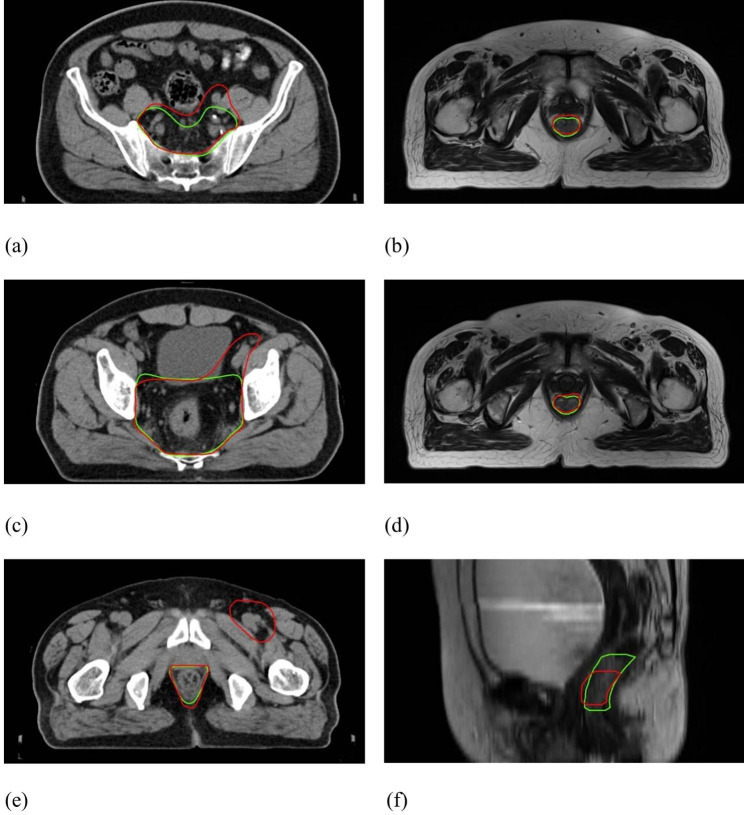

Representative illustration of outlier patient cases: (a)&(c)&(e) CTV contours of Patient K, where DSC = 0.84 and 95HD = 32.71 mm; (b)&(d)&(f) GTV contours of Patient S, where DSC = 0.64 and 95HD = 3.82 mm. (GT-red line vs. DL-green line)

Fig. 5.

Figure 3 shows the DSC and 95HD value distribution over the testing patient cohort, and Fig. 4 shows the CTV and GTV contours of a representative patient case (Patient D). For DL-based CTV segmentation (green squares in Fig. 3&), the DSC values range from 0.69 to 0.97 with mean ± SD as 0.85 ± 0.06, and the 95HD values range from 1.37 to 32.71 with mean ± SD as 7.75 ± 6.42. Two outlier data points in Fig. 3(b) are easily identified, i.e., Patient K with 95HD = 32.71 mm, and Patient B with 95HD = 15.50 mm. Representative axial images of Patient K are shown in Fig. 5(a)&(c)&(e), where the CTV-GT contour indicates this is a special case. The medical record shows that this patient was with perirectal lymph node invasion (LNI), and therefore mesorectal, sacral, internal iliac regions should be covered. This special treatment inevitable induced relatively large distance errors. This goes similarly with Patient B that required additional coverage of lymph nodes. When these two outliers are removed, the 95HD values range from 1.37 to 8.1 (5.93 ± 1.55).

For DL-based GTV segmentation (blue squares in Fig. 3), the DSC values range from 0.64 to 0.94 with mean ± SD as 0.87 ± 0.07, and the 95HD values range from 2.38 to 8.70 with mean ± SD as 4.07 ± 1.67. An outlier data point in Fig. 3(a) is easily identified, i.e., Patient S with DSC = 0.64. Representative GTV contours of Patient S are shown in Fig. 5(b)&(d)&(f). The GT and DL contours are highly similar in the middle axial planes, whereas DL contours exhibit over-coverage of surrounding tissue in the superior-inferior direction, which we did not figured out why yet and will be investigated in future.